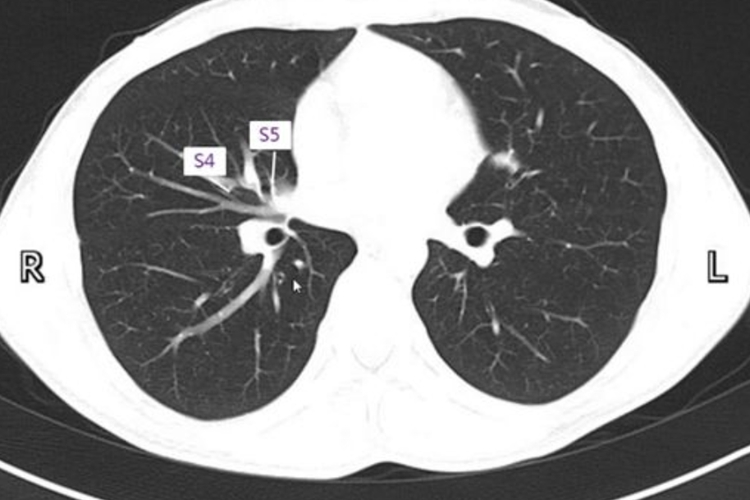

两肺野内含气而呈极低密度影,可见由中心向外围走行的肺血管分支,由粗渐细,上下走行或斜行的血管则表现为圆形或椭圆形的断面影。叶间裂可清楚显示为高密度线状影;肺段的基本形态为尖端指向肺门的锥体状;肺小叶呈圆锥形。